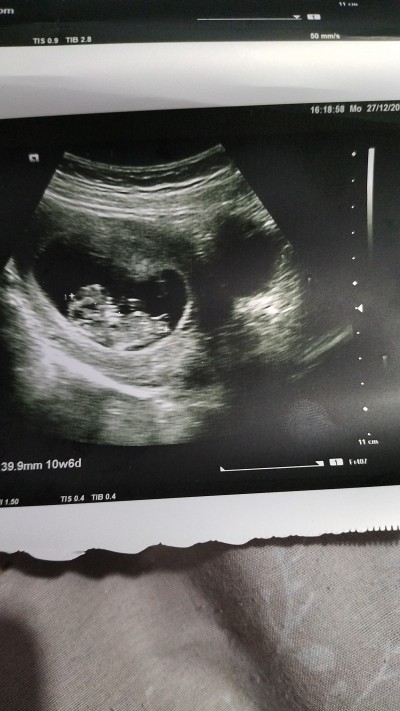

Çocuğumun cinsiyetini çok merak ediyorum kısmı erkekmi tahmin alabilirmiyim acaba

Bu bebek kız %100 diyor ve sonucu bekliyorum. :)

Göremiyorum hanımefendi, ama gece post açmıştınız orda gördüm ve cevap yazdım çok belirsiz belli olmuyor nub diye. Zaten sizin haftanız ileri öğrenmiş olmalıydınız şimdiye kadar, devlete mi gidiyorsunuz bu doktorlar neden söylemiyor anlamadım.

Kız bu bebek canım dedi dersin haber ber mutlaka

Kız geçti içimden

Kesinlikle kizzzz

Kiz canim kiz :)

Kız gibi nub a bakinca hayirlisiyla dogsun canim